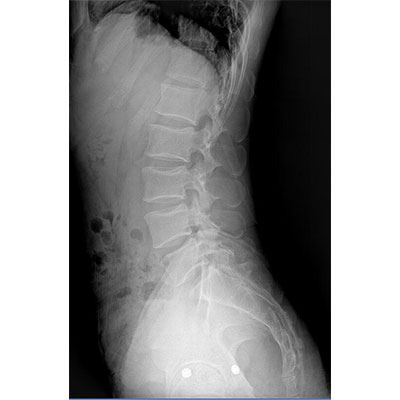

● 采用自主研發的技術,在保證優質圖像的前提下,大大降低X射線劑量,用心呵護醫護工作者及患者的健康。

● 短曝光時間,便于老年人、兒童、殘疾人進行臨床拍攝。避免這類群體因不能有效控制身體運動等因素造成的運動偽影,提高攝片質量及效率。